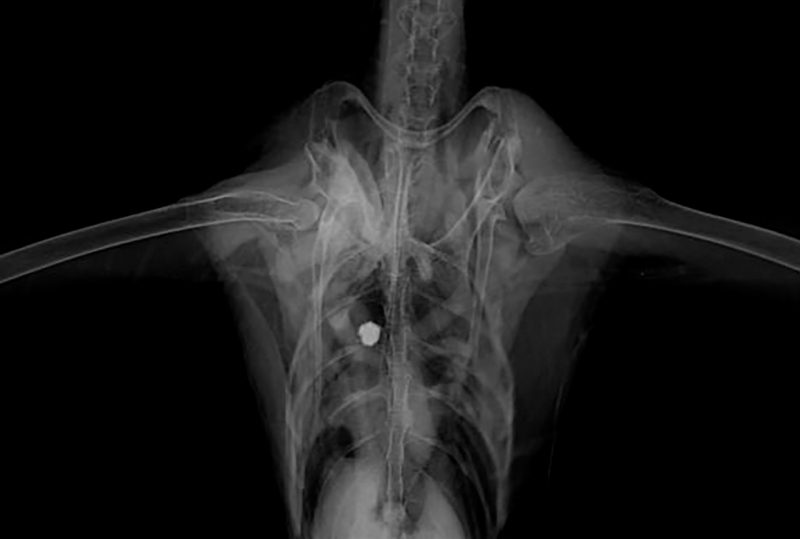

Após fazer um exame de raio-x, foi constatado que a ave não conseguia voar por conta da presença de um projétil alojado na musculatura peitoral – Foto: Divulgação/R3 Animal/ND